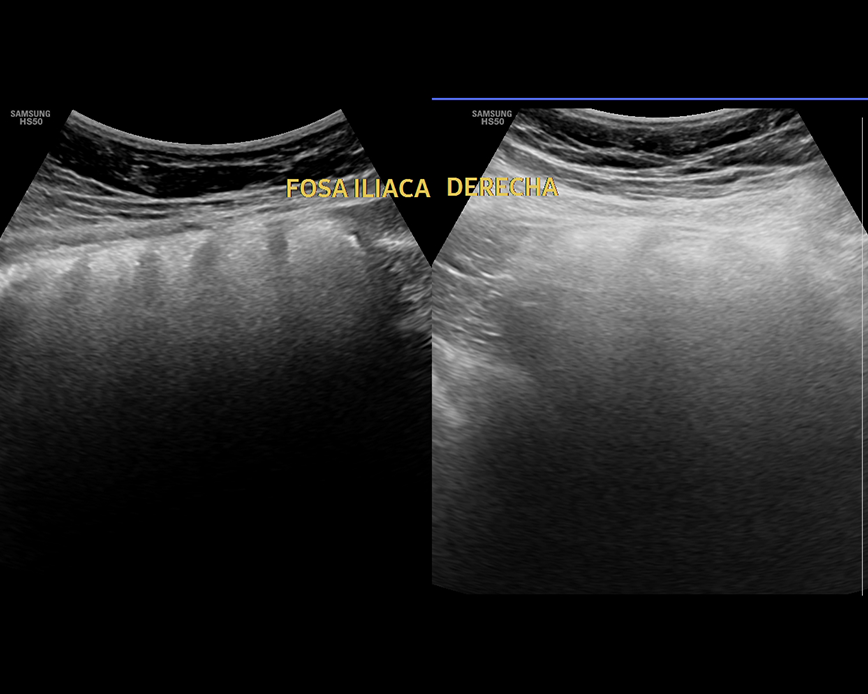

Ecografía Abdomen superior

- Evaluación del dolor abdominal